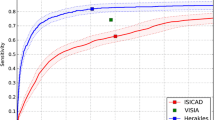

Figure 3 presents the distribution of the probability indices for the target and non-target areas. The mean probability indices of the target and non-target areas were 73.4 (95% confidence interval [CI] 70.4–76.4) and 43.6 (95% CI 40.9–46.3), respectively, indicating a significant difference (p < 0.001). Table 3 presents the details of the non-target areas. A total of 339 non-target areas (0.85 per image) were detected in 206 patients. Among these 339 non-target areas, 244 were non-target abnormal areas (0.61 per image), and 95 were non-target normal areas (0.24 per image).

Histogram of the probability index of the target and non-target areas. The X-axis represents the probability index for target and non-target areas. The y-axis represents the number of areas. The probability index of the target areas is significantly higher than that of the non-target areas (p < 0.001)